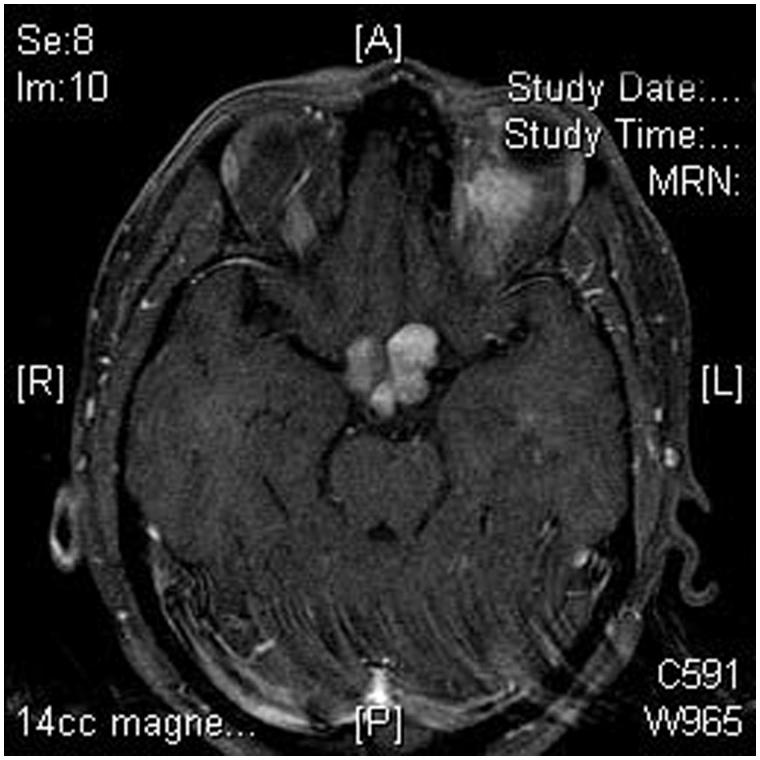

视神经胶质瘤(ONG)是较常见的原发性视神经肿瘤,通常在生命的一个十年被发现。散发性视神经胶质瘤(OPGs)通常在8岁前出现。我们的病人是ONG文献中一个没...

原发性视神经胶质瘤是较常见的良性毛细胞星形细胞瘤(WHO1级),发生在儿童时期,病程缓慢。恶性视神经胶质瘤(WHO3级至4级)发生在成年期,并遵循一个具侵...

视神经胶质瘤在全部脑瘤中所占比例不到1%,但由于这些肿瘤中有四分之三发生在10岁以内的孩子,它们占全部儿科大医院脑瘤的4%到6%。这些肿瘤大多发生...